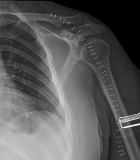

T.S. - 44 year old male with six month history of an anterior shoulder mass

Zoom image: Radiological image Radiological image.